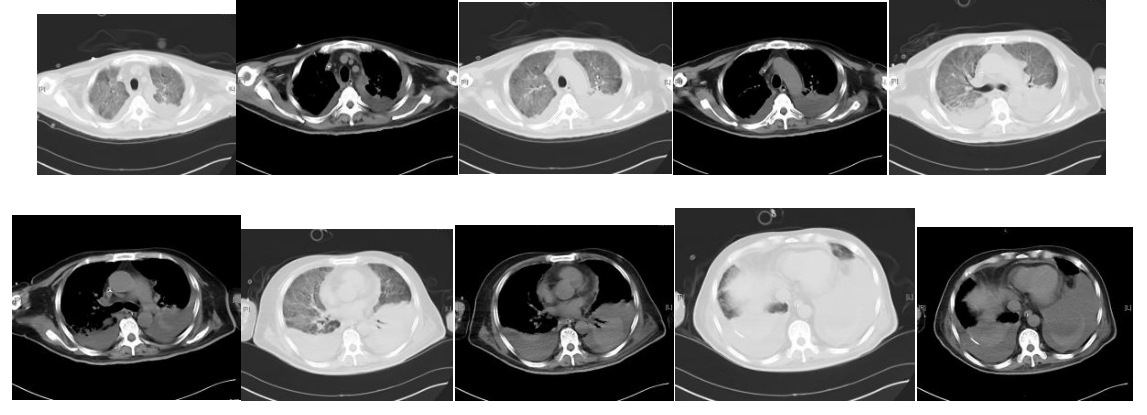

疗效评价:患者未再发热。神智清楚、言语欠清楚,左侧肢体肌力进一步下降。呼吸衰竭相对稳定,氧合指数维持在200 mmHg以上。血象无明显恢复,仍是持续粒细胞缺乏、中度贫血、血小板减少(波动在2万~5万)。7月28日复查胸部及头颅CT:双肺病变加重并出现双侧大量胸腔积液;右侧侧脑室、丘脑旁低密度,双侧上颌窦炎,真菌感染可能。再次行气管镜并送检灌洗液mNGs。并双侧胸腔置管引流,提示渗出性胸腔积液,留取胸水送检mNGS。灌洗液及胸水mNGs仍提示嗜肺军团菌。患者出现的肢体功能障碍,明确为脑梗塞导致,因患者持续存在血小板低下及凝血功能异常,未予抗凝及抗血小板治疗。

图10. 胸部CT(2023-07-28)

图11. 头颅CT(2023-07-28)